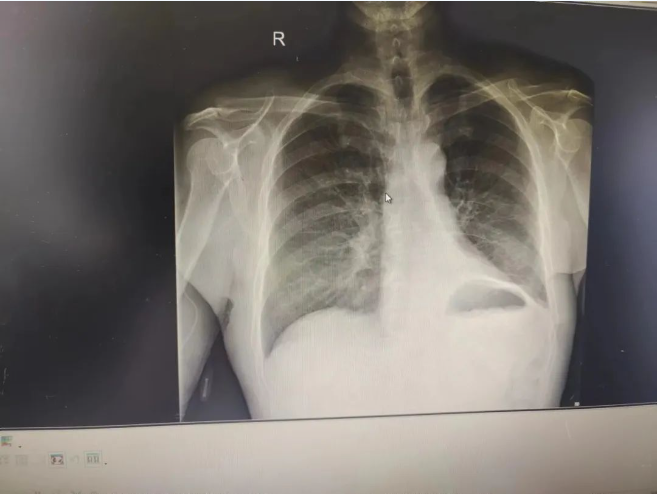

患者陈先生(化名),3周前体检发现左肺下叶背段包块,遂到医院胸心外科就诊,经检查诊断为“左肺下叶浸润性腺癌”,立即行相应手术治疗,术后给予相关对症治疗后病情平稳出院。目前,病情平稳准备行化疗术。

柯昌凤利用B超引导赛丁格技术,辅助心腔内电图定位技术,将导管尖端管道精准到达上腔静脉下1/3段,再由吴函秋于局麻下将港座埋植于右上臂肘上5厘米处后缝合,患者全术程生命体征平稳,NRS评分3分,术毕步行离开置管室。解决了陈先生的大难题!(供稿:胸心外科 柯昌凤)